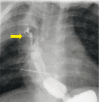

A pediatric case of endoscopic fistula closure using a polyglycolic acid sheet